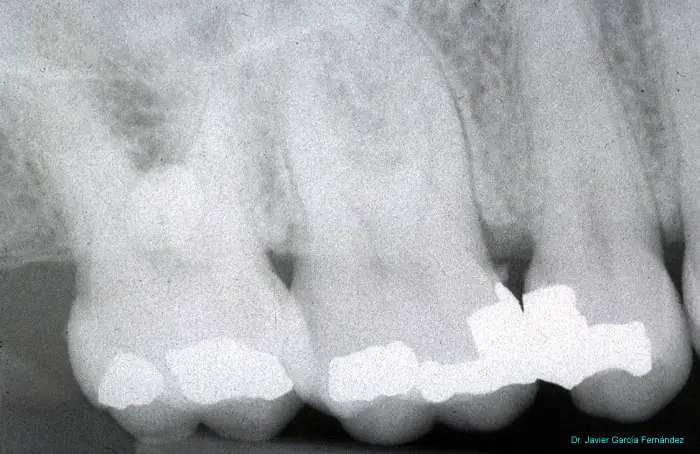

imagen 431